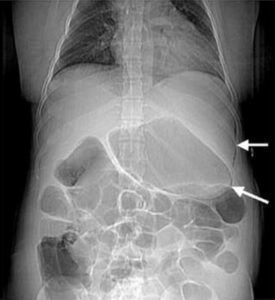

- гастрит; патології жовчовивідних шляхів; виразкові коліти; непрохідність кишечнику; запальний процес в сегментах травної системи та ін;

Непрохідність кишечника - розлади в органах грудної клітки (кісти; пухлини; бронхіт, травми; аневризми аорти; запалення легенів; зоб та ін);

Непрохідність кишечника